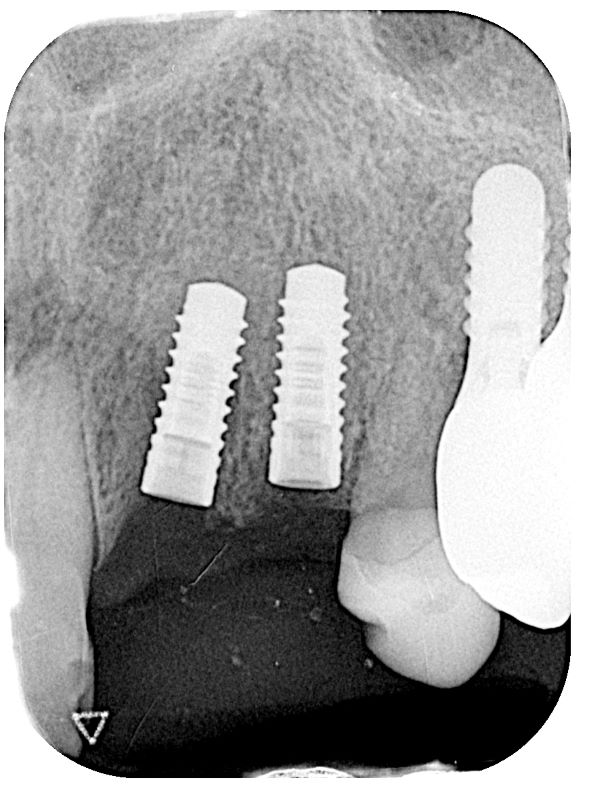

こちらがインプラントを入れた後のレントゲン写真になります。

②インプラント手術は、部分麻酔のもと1時間ほどで処置が完了しました。

今回のケースでは骨の幅が薄かったため、インプラントを埋める処置と同時に骨造成術という骨を作る治療も行いました。